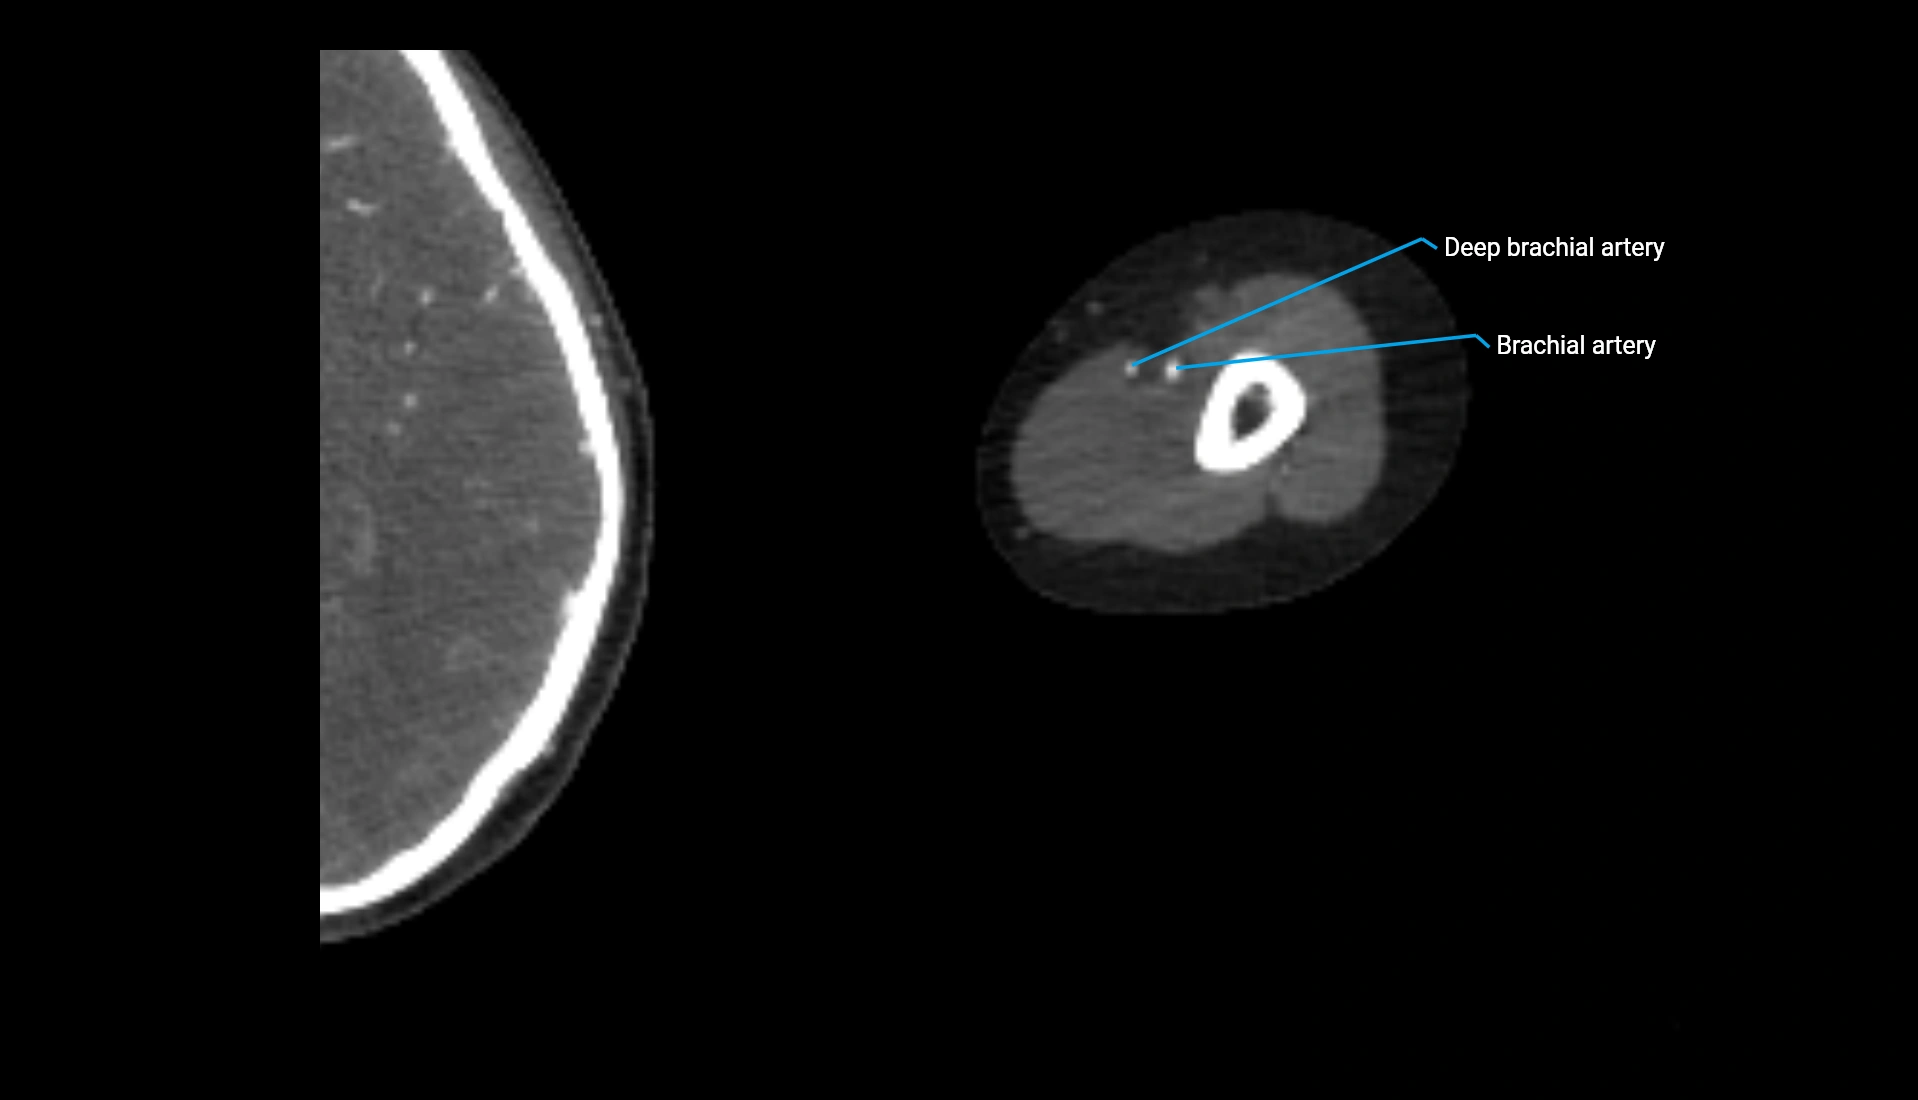

CT Appearance

Non-Contrast CT:

• Cortex: High-density, sharply defined

• Subchondral bone: Dense cancellous matrix

• Articular surface: Smooth concave contour articulating with the capitellum

• Excellent for evaluating bone integrity, alignment, and subtle fractures